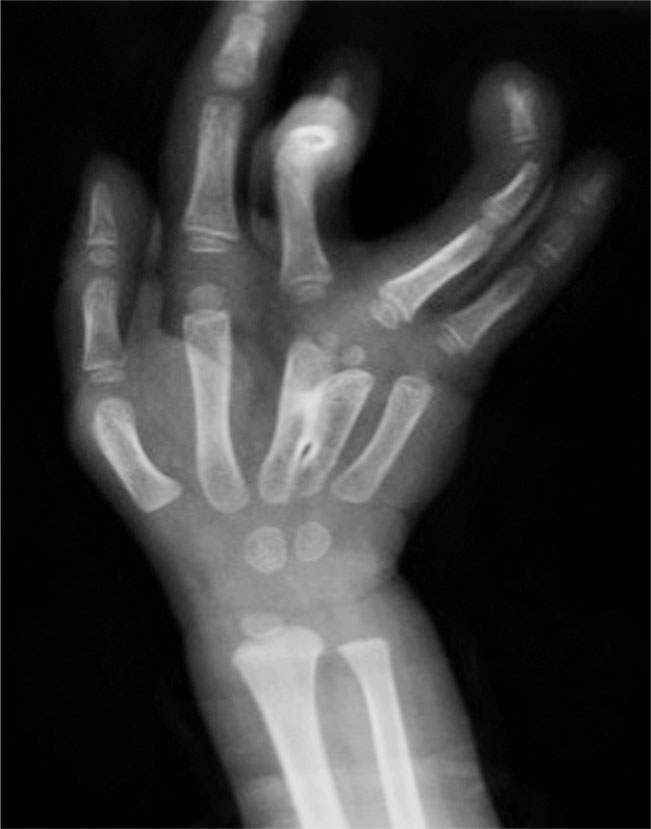

图1-2-21 全肘关节骨性融合病例

A.左侧前臂尺侧纵列发育不良;B.X 线片显示左侧肱骨桡尺骨融合(全肘关节融合),合并尺骨发育不良(尺骨远端部分缺如),桡骨继发性侧弯,第Ⅰ、Ⅱ及第Ⅳ、Ⅴ掌骨融合